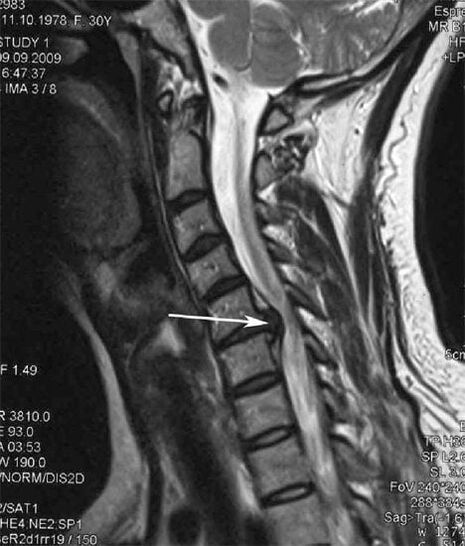

V počátečních stádiích je osteochondróza detekována pomocí MRI. Později může být patologie diagnostikována pomocí radiografie. Na rentgenových snímcích krční páteře je patrné snížení vzdálenosti mezi obratli, patologické změny ve fasetových kloubech a osteofytóza.

| Cervikální osteochondróza | Výskyt patologických změn v jednom nebo více segmentech pohybu páteře. Porucha pohyblivosti páteře, rozvoj myofasciálních bolestivých syndromů a skřípnutí míšních kořenů | Bolest, parestézie a motorické poruchy v cervikální oblasti, které se šíří do zadní části hlavy a horních končetin. Detekce charakteristických změn páteře na MRI a rentgenových snímcích (osteofyty, zmenšená vzdálenost mezi obratli, známky poškození meziobratlových kloubů) |

Mnoho lidí si stěžuje, že nemohou otočit krk kvůli silné bolesti, která se objeví po náhlém zvednutí něčeho těžkého. Tento jev ukazuje na tvorbu herniovaného disku. Příčinou bolestí zad, krku a horní končetiny je skřípnutí jednoho z nervových kořenů vycházejících z míchy.